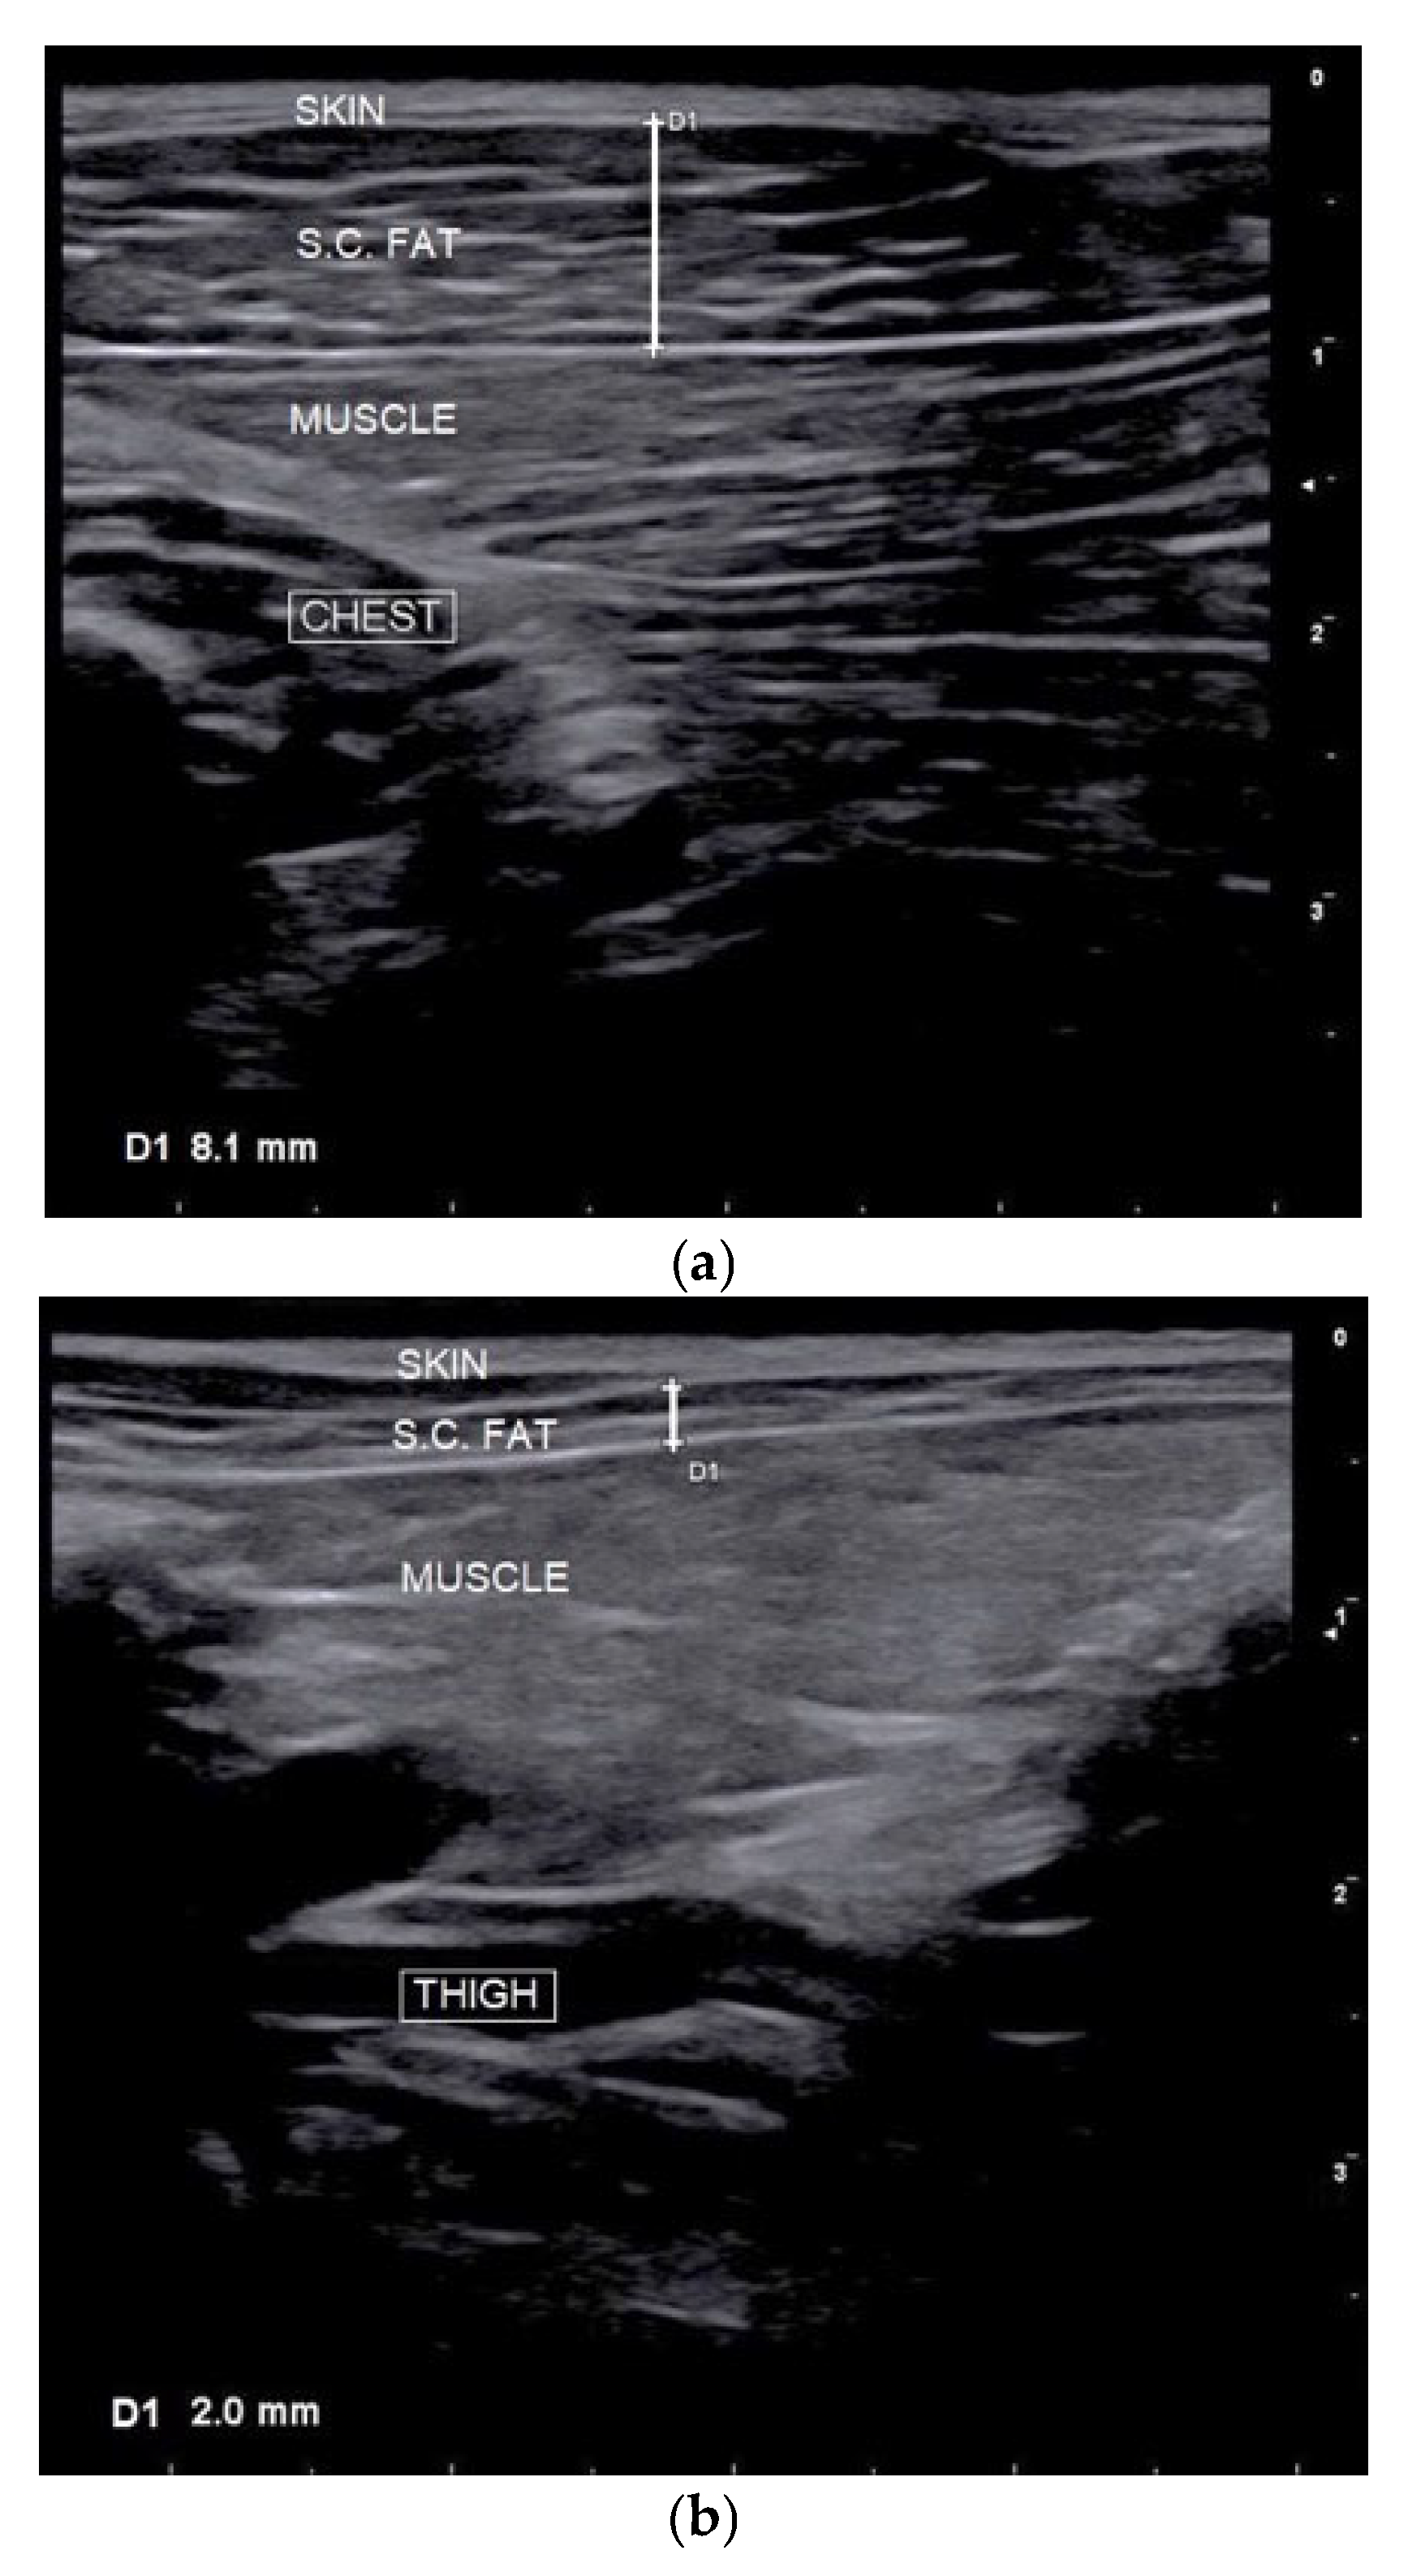

2.2.3. Subcutaneous Fat Thickness (SFT) Measurement